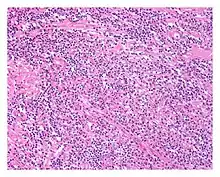

| Low power view of IgG4-related prostatitis. The prostatic stroma shows a dense inflammatory infiltrate and fibrosis (H&E, 100x) | |

The diagnosis of IgG4-related prostatitis could be made from histological examination if prostate biopsy or surgery has been performed.[6] The hallmark histopathological features of established IgG4-related disease are storiform fibrosis, a dense lymphoplasmacytic (lymphocytes and plasma cells) infiltrate rich in IgG4-positive plasma cells, and obliterative phlebitis.[7]